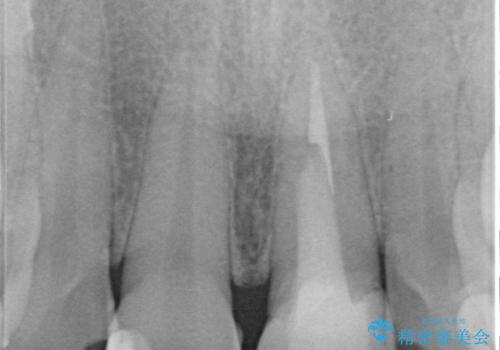

- 前歯の見た目を良くしたいとのことで来院された患者様です。今までに保険のプラスチック(コンポジットレジン)で虫歯の治療をしており経年的な劣化により着色が目立つようになっていました。また歯と歯の隣り合っているところに段差もあり虫歯になっていたり、詰め物も外れていたため前歯4本のオールセラミッククラウンによる治療を行うこととなりました。

拡大鏡視野下で保険のプラスチック(コンポジットレジン)、虫歯、左上1の被せものを除去し、オールセラミッククラウンに適した形にしました。